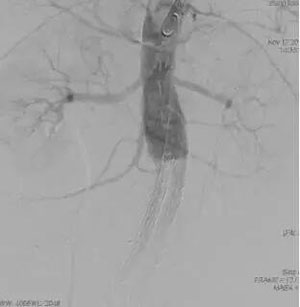

在金星教授的精心指导下,张十一主任医师团队(张十一主任医师、董典宁副主任医师、王默副主任医师、徐磊主治医师、王茂华主治医师等),本着以治病救人为第一要务的原则,群策群力,率先在省内联合应用三分支开窗重建技术及3D打印技术(图3)建立足够的锚定区来腔内修复复杂腹主动脉瘤,获得了圆满成功(图4,图5),通过新技术解决了原来不能解决的问题,挽救了患者的生命,达到了国内领先水平,将来会为类似患者的救治提供了新思路,必定会挽救大量患者的生命。

图3

图4

图5